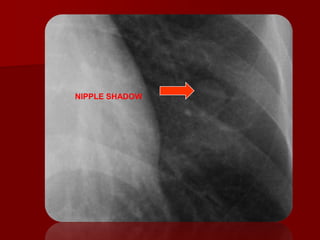

SOFT TISSUE

Soft tissues cast shadow on plain radiographs

which have less dense radio-opacity.

 Breast shadow result in increased opacity over

the lower thorax bilaterally.

 Nipple shadow may appear as round opacities in

the 4th or lower ant. Intercostal space.

 Breast and nipple shadow are usually bilateral

and symmetrical.

NIPPLE SHADOWS

NIPPLE SHADOW